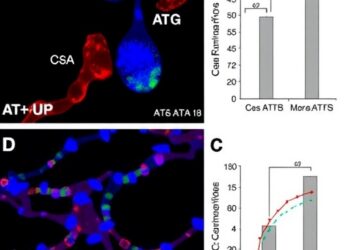

CsA+ATG Outperforms CsA Alone in Pediatric Aplasia

In a groundbreaking development poised to reshape the treatment of pediatric moderate aplastic anemia (MAA), researchers have unveiled compelling evidence...